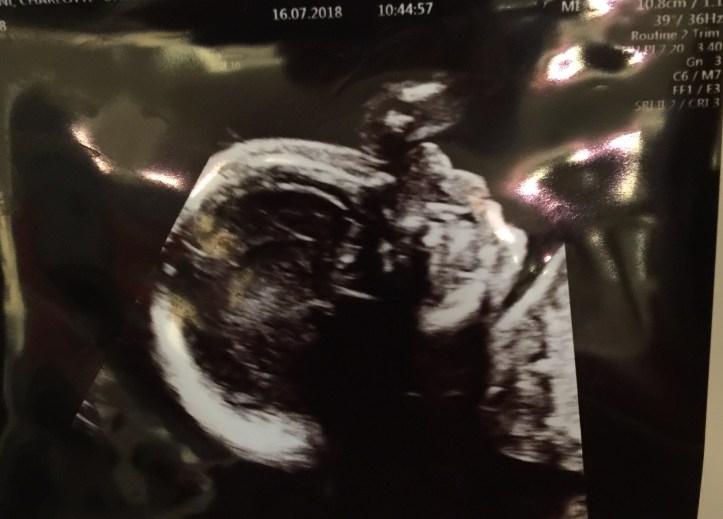

We were so excited to be going into the Rosie wing of Addenbrookes hospital in Cambridge. We laugh with the sonographer about how much of a wriggler this baby is, and she tells us to go for a walk as she can’t see everything she needs to.